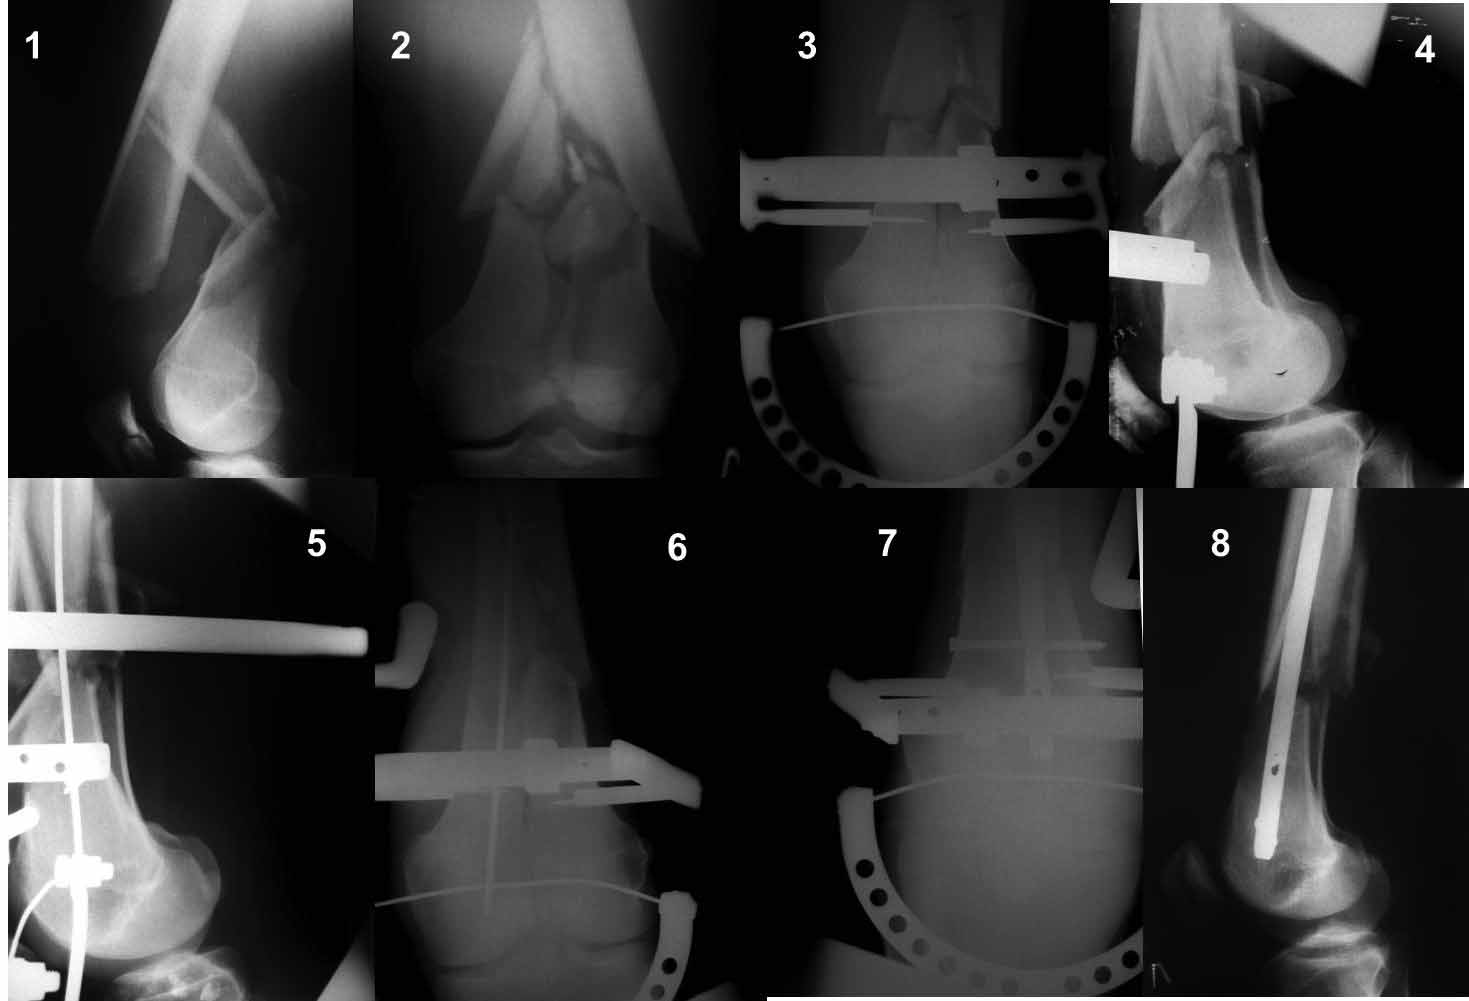

Переломы не слишком низкие для LCP и ретроградного стержня?

Нет, не слишком. Самый раз!

Ну зачем же так. Всё-таки считается "золотым стандартом". Во вложенном файле коллаж из сохранившихся фотографий одной из операций. Всё сделано закрыто и без ЭОПа.